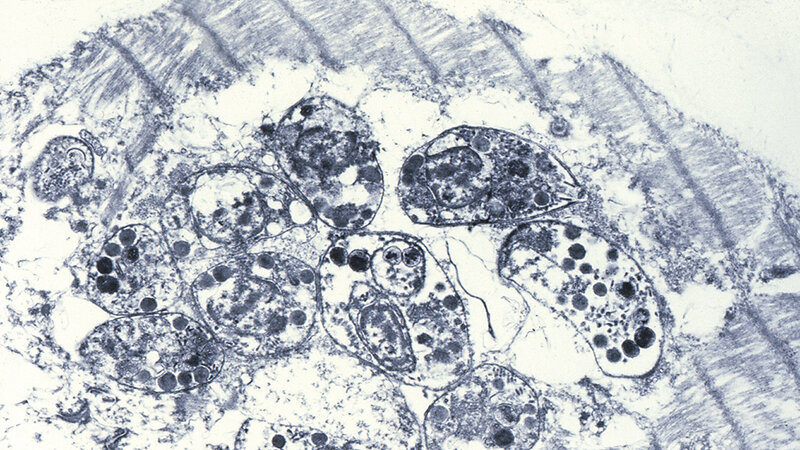

Zur Diagnostik der Toxoplasmose stehen in Abhängigkeit von der klinischen Symptomatik und der Immunkompetenz verschiedene diagnostische Methoden für den Nachweis von Toxoplasma gondii beziehungsweise vorwiegend dessen DNA sowie serologische Testverfahren zur Verfügung. Eine besondere Bedeutung hat die Labordiagnostik für die Primärinfektion während der Schwangerschaft mit daraus resultierender pränataler Infektion des Kindes. Um das Risiko für eine diaplazentare Übertragung von Toxoplasma gondii abzuklären, kann der DNA-Nachweis aus Fruchtwasser ab der 18. Schwangerschaftswoche mit der PCR erfolgen. Die Pränataldiagnostik beim Neugeborenen erfordert eine Kombination verschiedener serologischer Testverfahren und dem direkten Erreger- oder DNA-Nachweis mittels PCR.